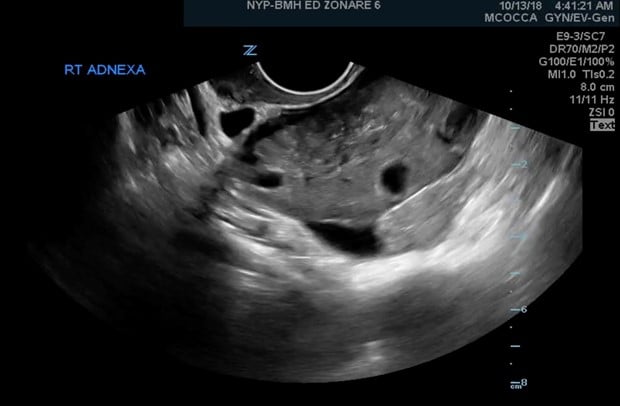

Figure 1. Ovarian torsion with absent flow

Ovarian torsion occurs usually secondary to ovarian cysts or masses, predisposing the ovary to twist. As the ovary twists, so does the vascular supply, initially leading to blockage of venous return. This blockage leads to ovarian congestion, producing some of the key signs seen initially on pelvic ultrasound: enlargement of the ovary and peripheralization of the follicles. As the ovary becomes increasingly congested, the distal part of the ovary begins to lose its arterial blood flow, ultimately leading to ischemia and necrosis, as seen in Figure 1. However, ovarian torsion does not necessarily occur in this order. In addition, the absence of either the arterial or venous flow, or the presence of both may be observed.2 Identification of torsion before this time is key and necessary for salvage of the ovary.4